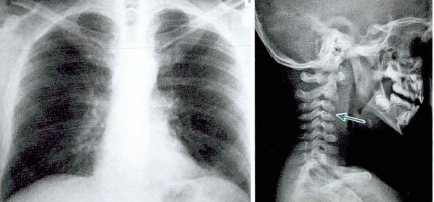

사진 찍어서 어딘가 찌그러져 보이는데 신기하게도 농양 때는 열이 나지 않았어!

항생제 진짜 계속 맞고 농양이 있는데 가라앉아서 빼달라고 안 해도 된다고 했어.후, 다행이다~~~